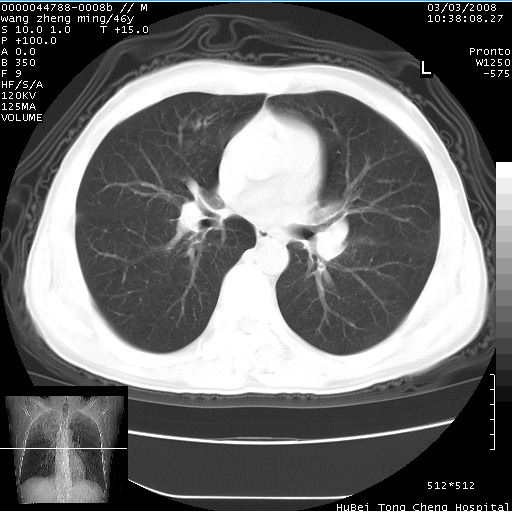

以下是引用卜一在2008-3-22 1:37:00的发言:[br]右肺实质性肿块,边缘不整,明显见毛刺征 分叶征及胸膜凹陷征,右上叶支气管明显变窄,远端散在的片状 斑片状实变影。另:左肺门较大肿块,支气管受累 变窄,远侧见阻塞性肺炎。纵隔内见肿大淋巴结。多考虑:右肺周围性肺癌伴左肺门 纵隔淋巴结转移!